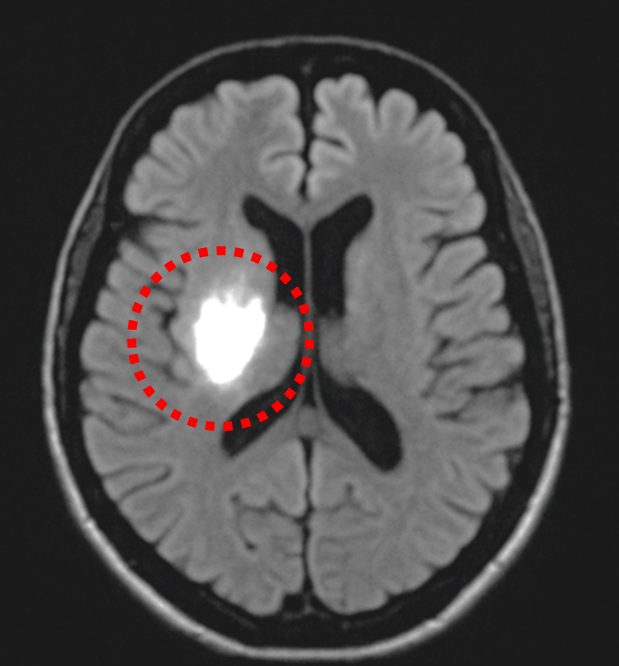

○背骨や脳の検査

MRIは、脳梗塞や脳腫瘍、手足や背骨などの整形外科領域に優れています。